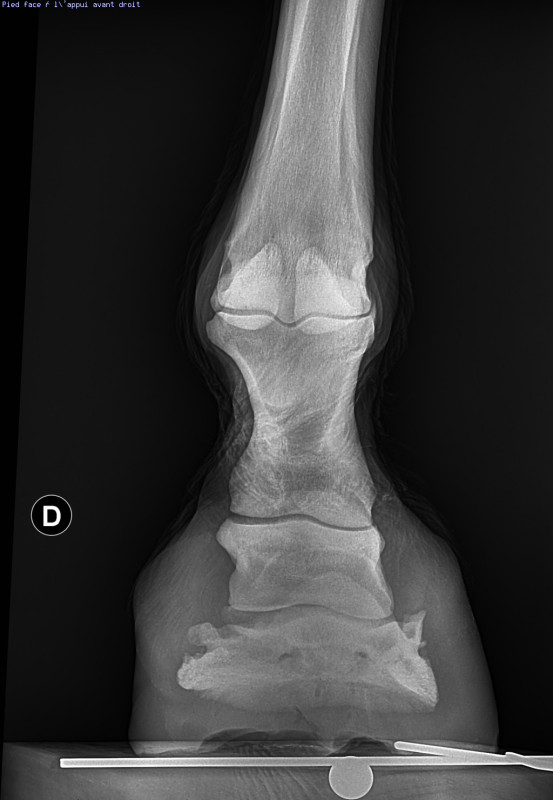

C’est un antérieur droit, pris de face. On voit qu’il y a un déséquilibre latero médial et que le cartilage est affiné en interne. Si on mesure la distance de P3 au sol, on dirait que P3 est plus haute en externe, mais du coup je ne comprends pas pourquoi c’est le côté interne qui est pincé.

La vétérinaire était pas capable de me dire ce qu’il fallait faire en parage, de quel côté il fallait rabaisser. Le talon interne a tendance à être plus haut, donc si je suis mes repères habituel, c’est celui ci que je dois légèrement baissé, mais je ne trouve pas cela logique avec la radio.